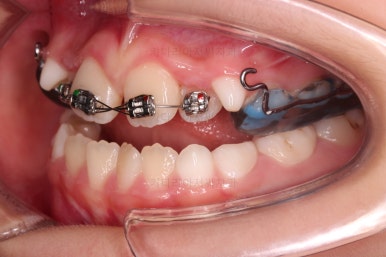

마찬가지로 초진 시 입안의 모습이에요.

아래 앞니가 윗니보다 앞에 있는 "반대교합" 즉, 거꾸로 물려있는 상황이었고요.

어금니 쪽을 보시면(왼쪽 위 사진) 윗니 어금니도 아래 어금니보다 안쪽으로 들어와 있는 "어금니 반대교합"도 있는 상황이었어요.

즉, 윗니가 있는 위턱뼈가 3차원적으로 작은 상황이었던거죠.

이렇게 아랫니들이 윗니보다 앞으로 나와있는 형태의 부정교합을 "앵글씨 3급" 부정교합이라고 합니다.